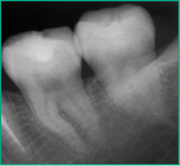

En 2013 concurre paciente de sexo femenino de 37 años de edad a la Clínica Integrada II UdelaR por caries profunda en pieza 37 (Fig. 2a). Se diagnostica CPPA ya que solo el test de fresado da positivo. Se planifica eliminación total de caries de paredes laterales con aislación absoluta. Se observa último test colorimétrico con rojo ácido 52 en propilenglicol (Detector, Pharma Dent, Uruguay) dejando fina capa de dentina infectada en pared axial (Fig. 2b) la cual se protege con mezcla de hidróxido de calcio (Ca(OH)2) puro con suero fisiológico y luego encima Ca(OH)2 fraguable (Life, Kerr, USA) (Fig. 2c). Se sella con ionómero vítreo (Gold Label Luting & Lining Cement, Tokyo, Japan).